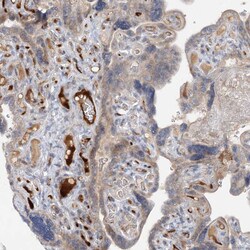

Invitrogen™ FGF19 Polyclonal Antibody

Brand: Invitrogen™ PA5111069

| Immunohistochemistry (Paraffin) | |